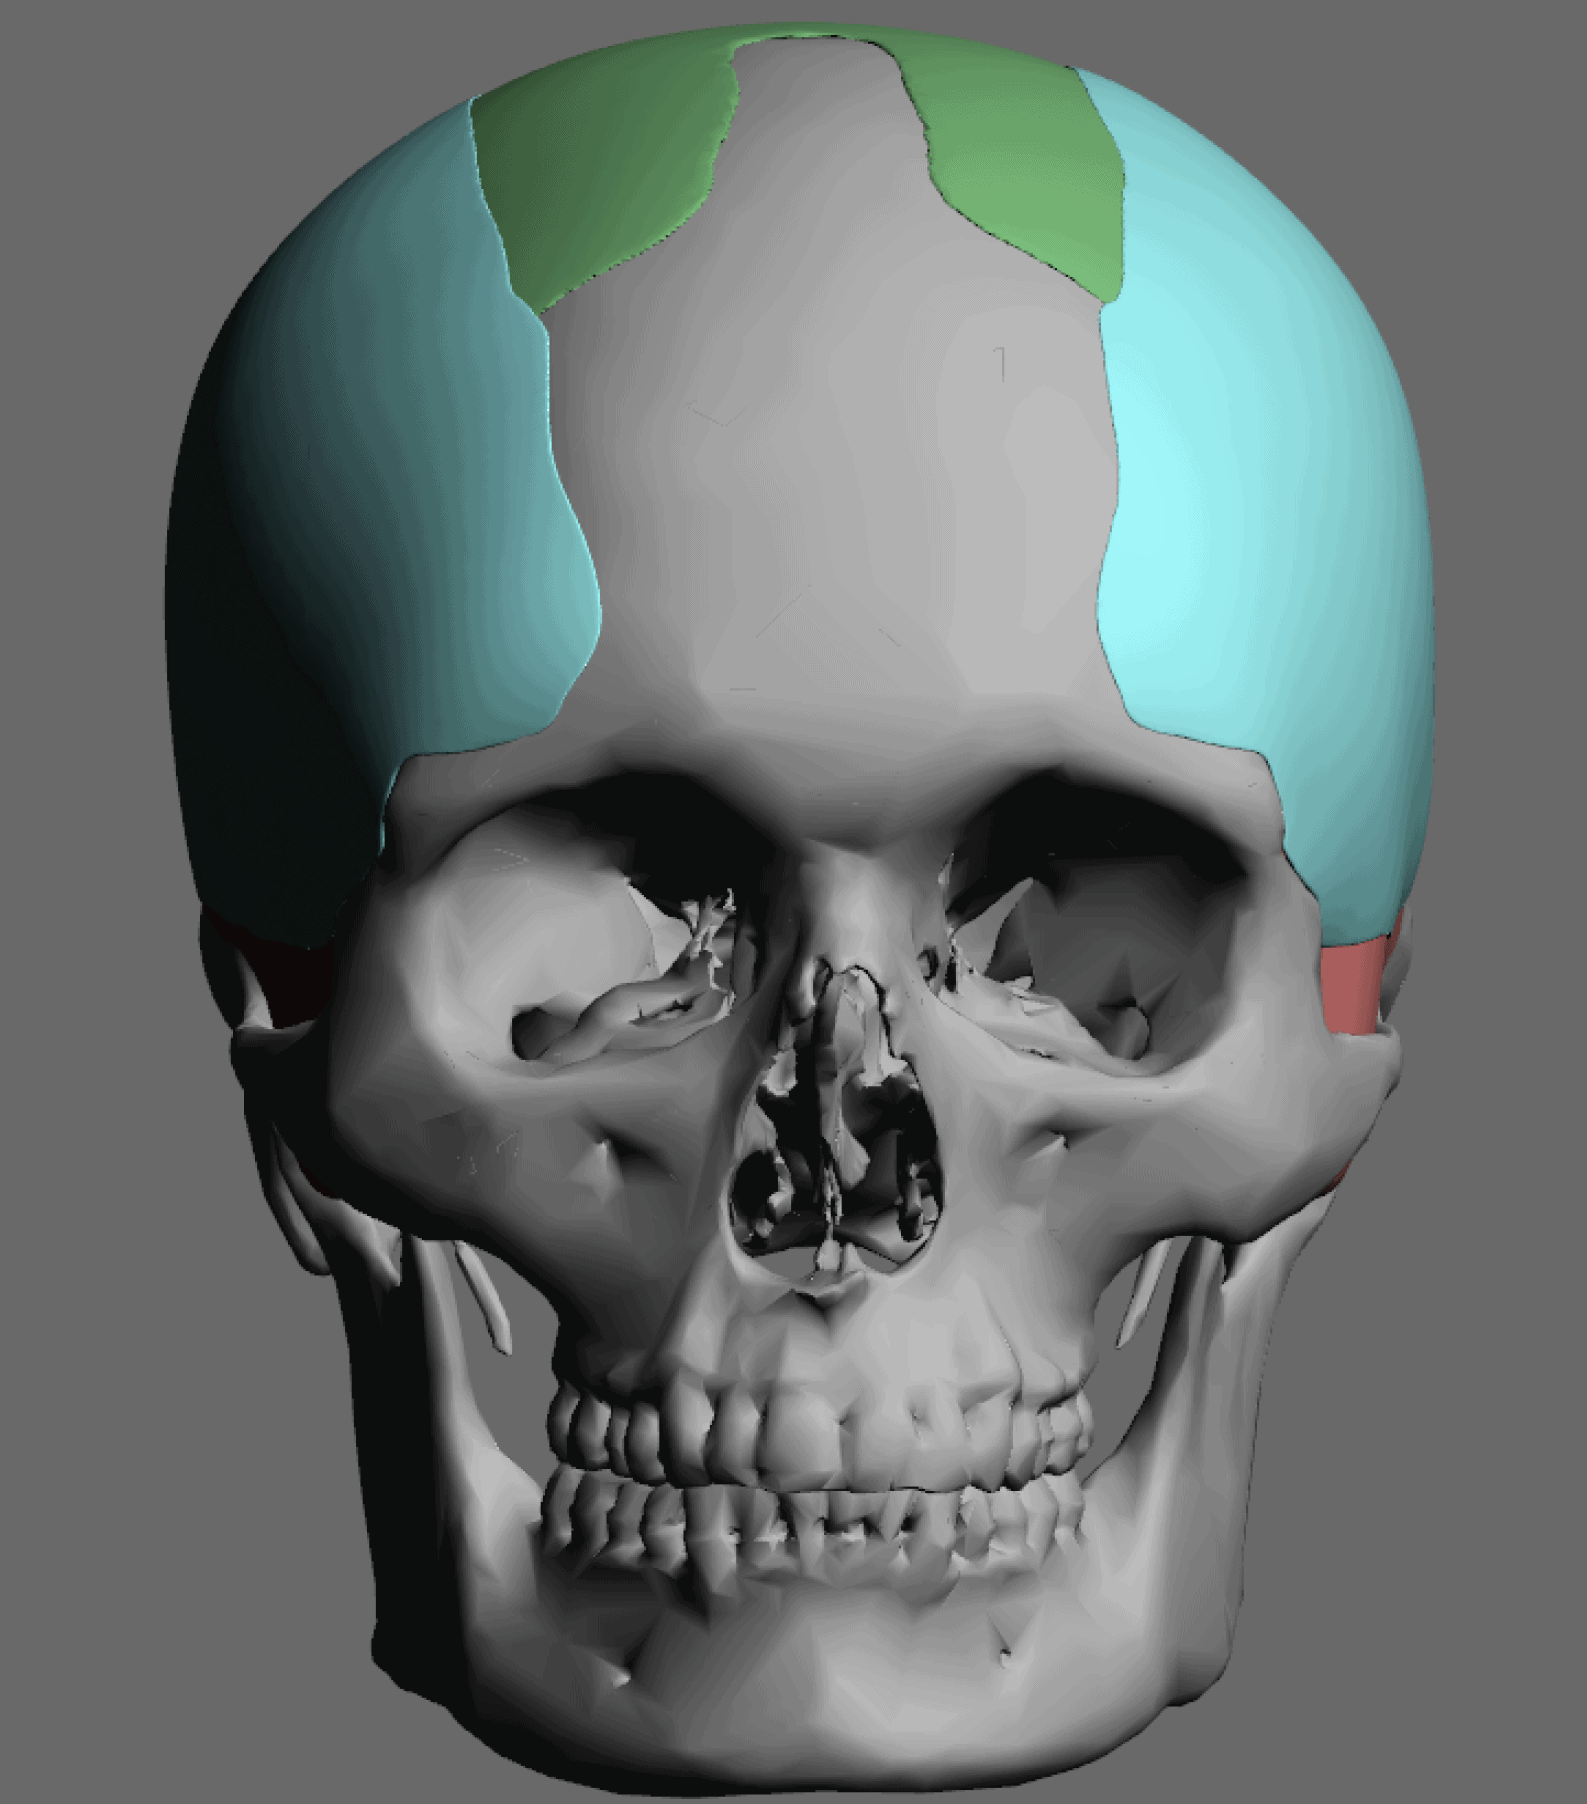

Desire for change of head shape from front view form an inverted V shape to a rounder and wider head shape.

Placement of custom extended forehead-temporal implants through incisions in the crease behind the ear. (he had a prior back of head skull implant which is green in the implant designs and which the head widening implants partially covered it)

Desire for change of head shape from front view form an inverted V shape to a rounder and wider head shape.

Placement of custom extended forehead-temporal implants through incisions in the crease behind the ear. (he had a prior back of head skull implant which is green in the implant designs and which the head widening implants partially covered it)